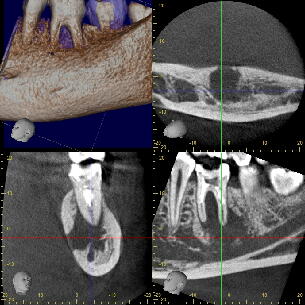

CT画像:当初病巣の下底は下顎管付近まで、また頬側の皮質骨にも穴が開いています

が、徐々に黒い病巣部分が小さくなってきている様子が分かります。 2.再植を応用した根の治療